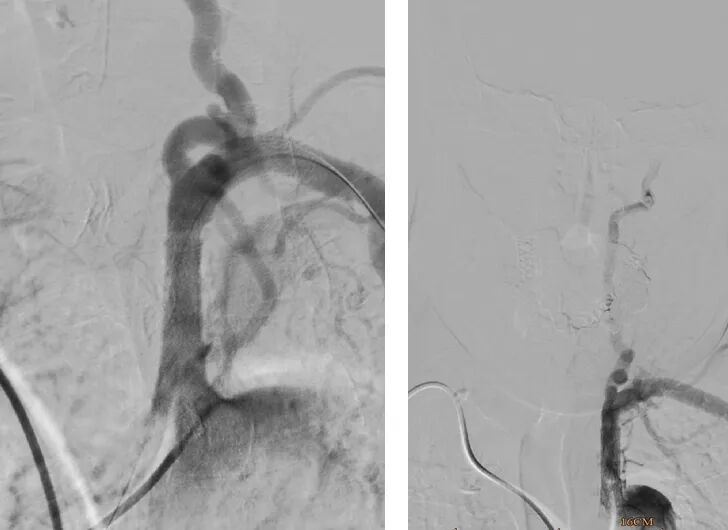

· 10-29mmOminiLink支架

▪18导丝送入18系统球囊预扩;

▪送入10-29mmOminiLink支架;

▪支架植入及植入后造影

支架覆盖理想,狭窄解除。